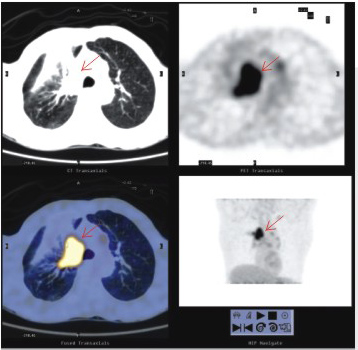

1.3.2 CT變現(xiàn)

CT是診斷腸系膜脂膜炎的有效方法,可明確顯示病變的范圍,提示病變?yōu)榱夹缘模瑢τ惺中g(shù)指征的病例可于術(shù)前準(zhǔn)確定位。通常以炎性細(xì)胞浸潤、脂肪壞死和纖維化的程度不同,CT變現(xiàn)各異。典型CT表現(xiàn)為圍繞系膜大血管(不受累及)、邊界清楚、密度不均勻的單個(gè)或多個(gè)軟組織密度腫塊(于腹膜后密度相比),其內(nèi)可見脂肪密度和低密度囊變區(qū),大血管和腫塊周圍見“脂肪暈環(huán)”,腸攀向四周移位。部分表現(xiàn)為系膜根部圍繞系膜血管的單個(gè)或多個(gè)以脂肪成分為主的腫塊,內(nèi)散在放射狀條索樣、結(jié)節(jié)樣(直徑<5.0mm)軟組織密度區(qū)(代表炎癥和纖維化)。有的表現(xiàn)為包膜的密度不均勻腫塊,內(nèi)有脂肪、水樣或軟組織密度區(qū)。少數(shù)變現(xiàn)為多房囊性腫塊(由于淋巴管和血管阻塞引起的淋巴管擴(kuò)張)。中心可見鈣化。